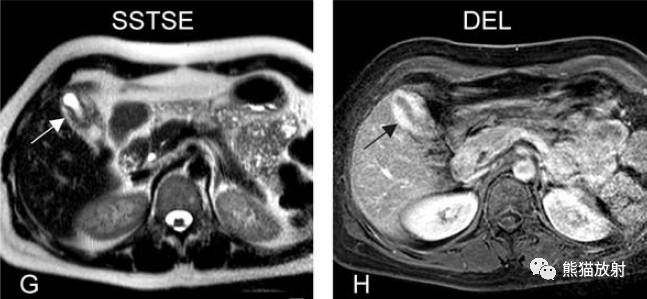

膽囊壁水腫

Gallbladder Wall Edema

膽囊壁增厚(并肝硬化、門脈高壓、腹水)。T2WI顯示膽囊壁因水腫而光滑均勻增厚,增強(qiáng)延遲期顯示強(qiáng)化的膽囊壁(內(nèi)外兩層:粘膜層和漿膜層),薄而清晰光滑。